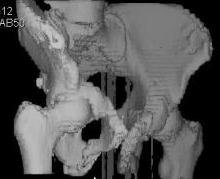

Уважаемые коллеги! Девушка 18л сросшиеся переломы лонных, седалищных костей с обеих сторон, перелом крестца справа,перелом костей голени справа (зио), 3 мес после травмы, АВФ снят с таза. Патологической подвижности нет. Стоит самостоятельно, ходит с костылями, поскольку 3 месяца практически не ходила. Беспокоит выступание лонной кости в области лобка, хотя объективно грубого косметического дефекта нет. На кт разворот лонной кости в сагиттальную плоскость. Вопрос: стоит ли добиватьсяполной репозиции или же достаточно произвести остеотомию верхушки выступающего отломка?

Предварительный диагноз- посттравматическая вертикальная нестабильная деформация таза II степени, неправильно срастающийся перелом боковой

массы крестца справа, правой лонной и седалищной костей, застарелый разрыв лонного сочленения.

Для уточнения диагноза ниеобходимы обзорные рентгенограммы таза (прямая и inlet), Кт срезы на уровне переломов для определения степени сращения и решения вопроса о методе оперативного восстановления анатомии (делать ли остеотомию, низводить ли задние отделы), ни о какой "остеотомии выступающих отломков" тем более у девочки 18 лет речи быть не может.

Предоставляю срезы. Если пациентку функционально ничего не беспокоит, стоит ли навязывать ей лечение.